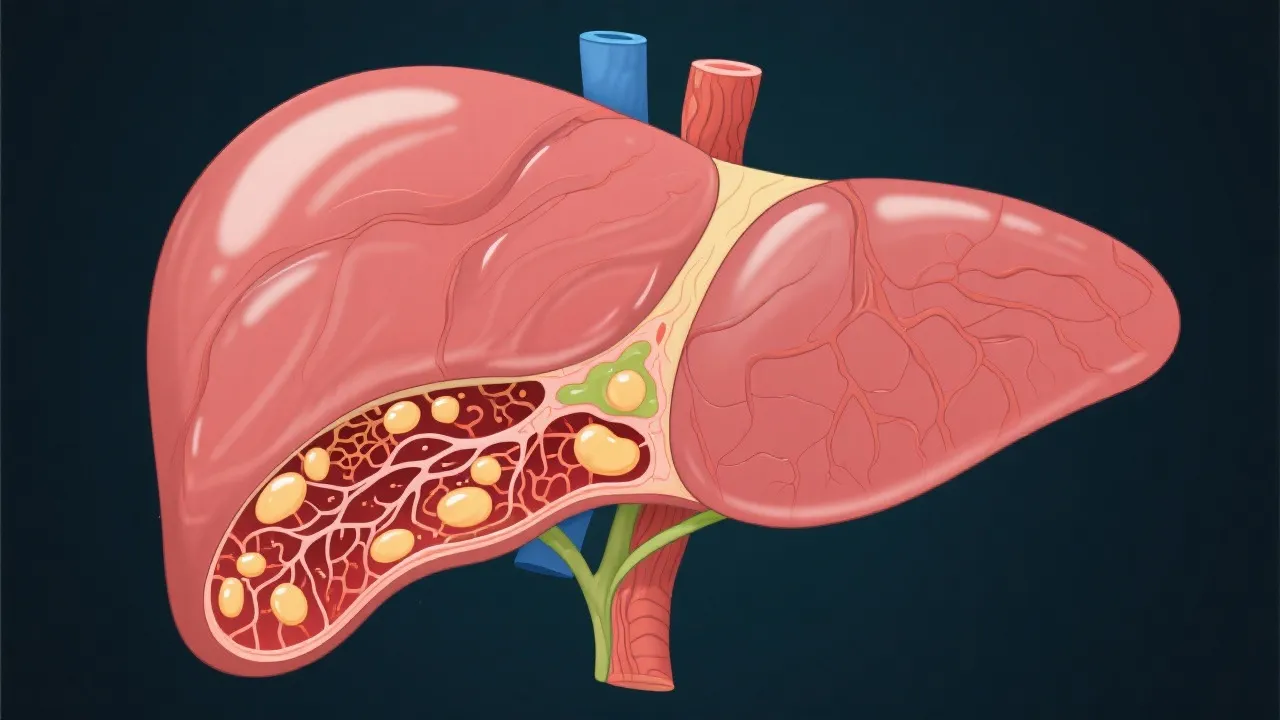

Liver transplantation is a life-saving procedure for patients with end-stage liver diseases, among which Nonalcoholic Steatohepatitis (NASH) stands out as a leading cause. NASH is a severe condition resulting from the accumulation of fat in the liver, leading to inflammation and damage, often culminating in cirrhosis and liver failure. This condition has emerged as an alarming health issue due to the increasing global prevalence of obesity and related conditions like diabetes, which have created a fertile ground for the development of NASH. As lifestyle-related conditions continue to rise, understanding NASH, its progression, and implications for liver transplantation has become increasingly important. Advanced cases of NASH often require liver transplantation, making it vital to have comprehensive strategies for managing and addressing this condition.

The correlation between NASH and liver transplantation is rooted in the liver's progressive damage due to fatty deposits and inflammation. NASH is characterized by lipid accumulation within hepatocytes, which triggers a cascade of inflammatory and fibrotic processes. As NASH progresses, it can lead to fibrosis and eventually cirrhosis, characterized by the liver's inability to function normally. In patients with NASH cirrhosis, the liver is unable to perform critical functions, including detoxification of harmful substances, regulation of metabolism, and production of essential proteins. Liver transplantation becomes critical in these cases, offering not only a chance at survival but also presenting an opportunity to restore liver function, enhance quality of life, and improve overall health outcomes. The possibility of regaining normal liver functionality makes this procedure an essential consideration for patients diagnosed with advanced stages of NASH.

NASH is often linked to obesity, type 2 diabetes, metabolic syndrome, and insulin resistance, leading to fat accumulation in the liver. Additional factors such as genetics and hormonal imbalances may also play a role in the development of the disease.